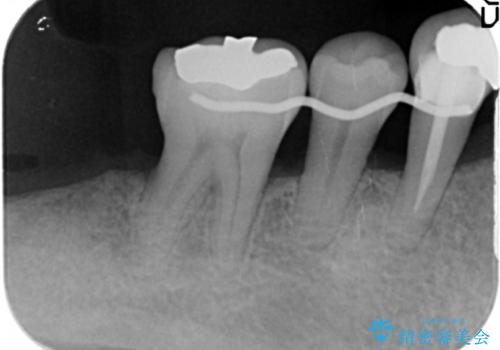

- 全顎的な重度歯周病の患者様です。

骨吸収の進行している右下臼歯部に、再生療法(骨を増やす手術))を行いました。

再生療法から1年後、リエントリー手術により骨の再生を確認し、骨外科処置(骨を平らにして歯周ポケットの根本的な改善を図る処置)を行いました。